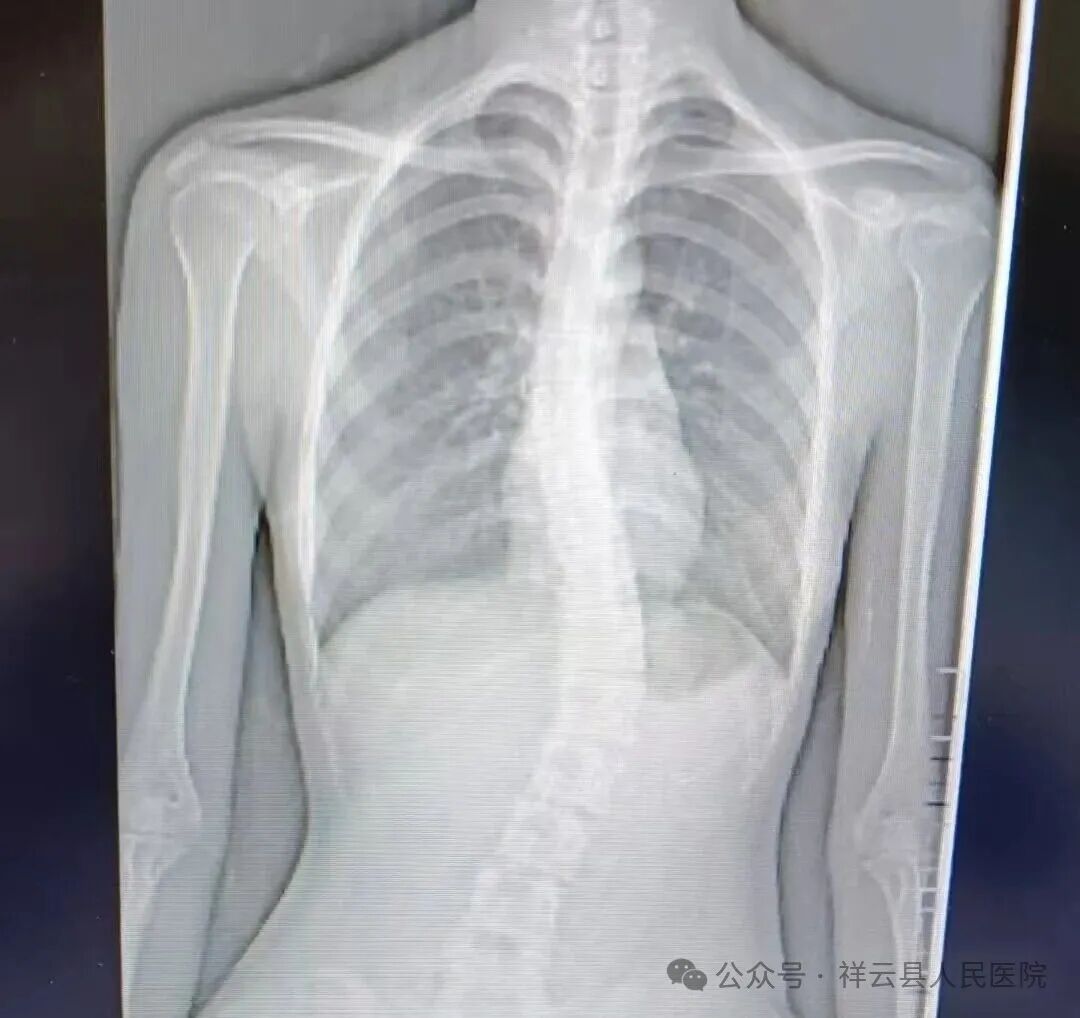

1.精准评估:采用脊柱全长X光片分析、体态评估、肌力测试等专业手段,明确侧弯类型、角度及功能障碍程度,为每位学员建立专属康复档案。